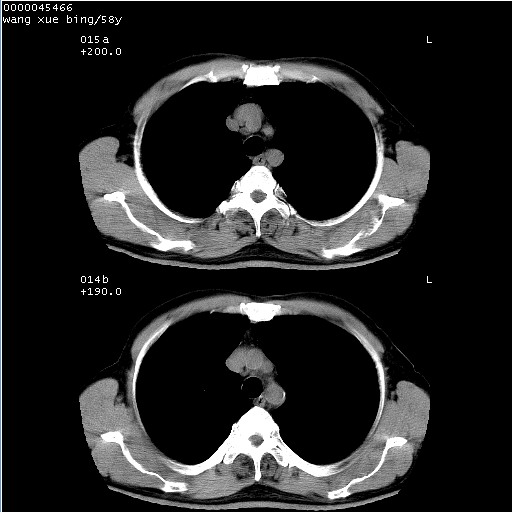

胸部ct轴位平扫(层厚10mm,螺距1.5,重建间隔10mm),图像如下:

考虑右下肺中心型肺癌并远端阻塞性炎症及胸膜及纵隔淋巴转移

支持癌性空洞并远端阻塞性炎症